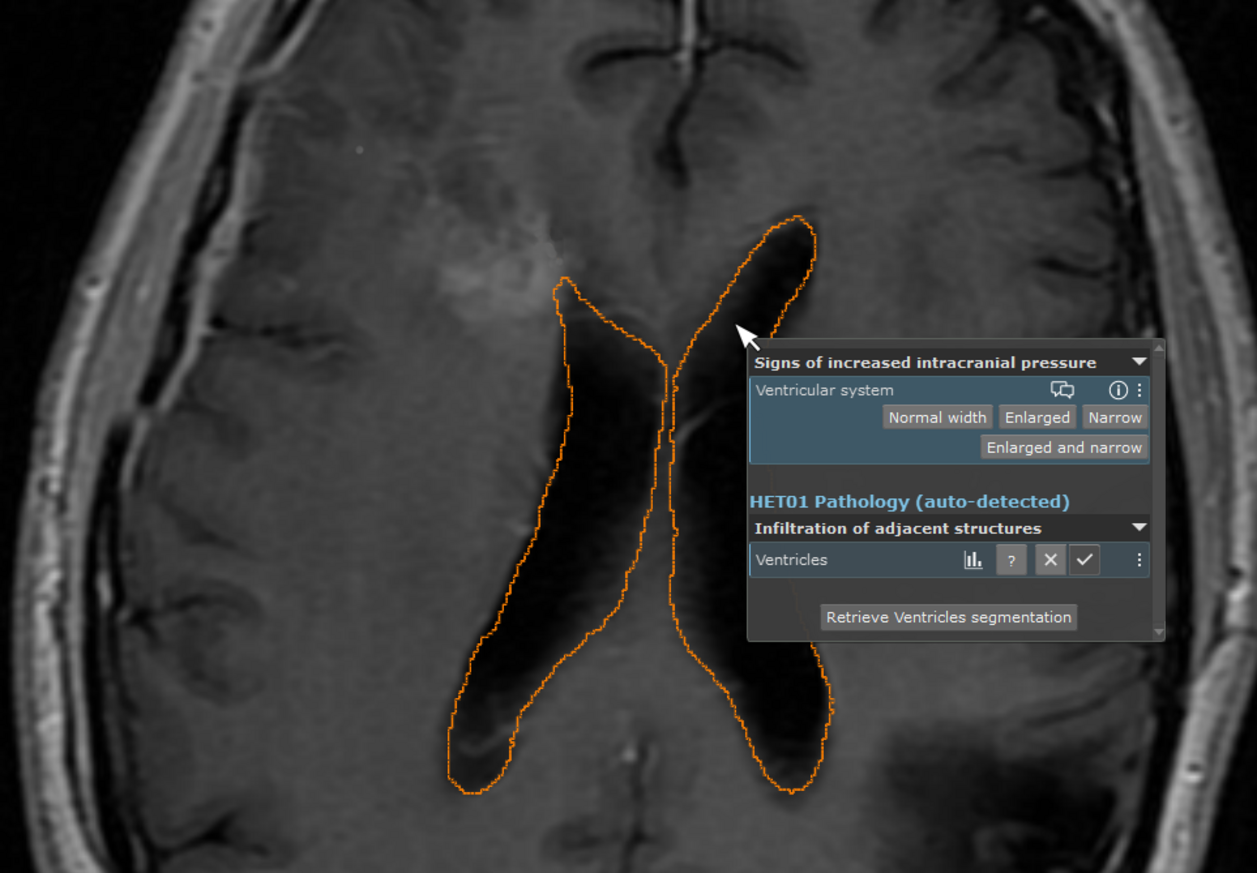

One of our first prototypic use cases is image/structure-aware filtering of questions/templates: By clicking on an anatomic structure inside the viewer, mint Lesion™ automatically detects the structure within the slice set and suggests the relevant questions. Another use case is the automated detection and full segmentation of cranial lesions, for effortless volumetric tumor monitoring applications. However, this is just a teaser of the functionalities that will be bound to come.